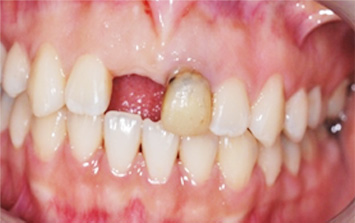

앞니 상실과 보철물 오염으로 내원한 환자분. 오른쪽 오염된 보철물로 인하여 잇몸이 올라간 상태, 치주치료와 올세라믹 치료를 하고

상실된 부위에 임플란트를 식립 하였습니다. 앞니의 경우 외모를 결정시키는 중요한 의미가 있기 때문에

자연치아와 구별 안될 정도로 자연스럽게 만들어 드렸습니다.